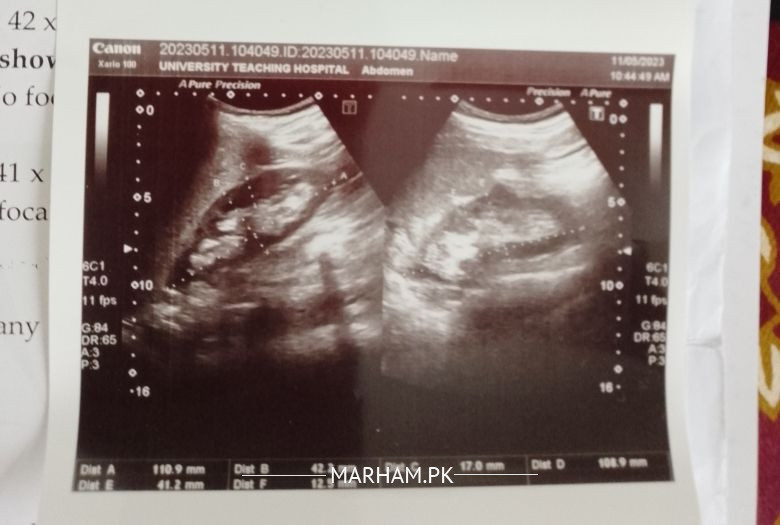

ultrasound shows calculus at VUJ, size 8.5mm.... it can be removed through medicine or requires surgery?